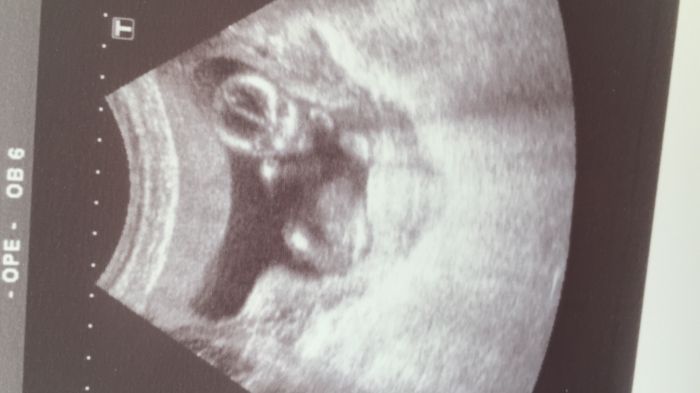

Ahoj tak já se k vám taky přidám :) už to tady chvilku čtu,ale neměla jsem potřebu něco přidávat..Je mi 25 čekáme první miminko jsem 14+6 a miminko se nám povedlo na první pokus a všechno je v pořádku :) chodím normálně do práce špatně mi bylvá večer a to už jsem doma..jen mě včera sejmula nějaká střevní chřipka tak jsem z toho byla trochu vyděšená ale dneska už je to mnohem lepší..12.12. mám kontrolu tak doufám že už se snad dozvíme co to je..na screeningu nám pan doktor řekl že je to malej ufon viz.fotka :D